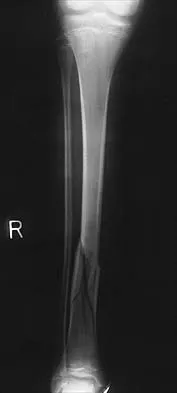

A 20-year-old man sustained a closed tibial fracture and is treated with a reamed intramedullary nail. What is the most common complication associated with this treatment?

Explanation

The most common complication is anterior knee pain (57%). The knee pain is activity related (92%) and exacerbated by kneeling (83%). Although knee pain is the most common complication, most patients rate it as mild to moderate and only 10% are unable to return to previous employment. Some authors report less knee pain with a peritendinous approach when compared to a tendon-splitting approach. In one study, nail removal resolved pain in 27%, improved it in 70%, and made it worse in 3%. The incidence of the other complications was: infection 0% to 3%, nonunion 0% to 6%, and malunion 2% to 13%. Compartment syndrome is rare after nailing. Court-Brown CM: Reamed intramedullary tibial nailing: An overview and analysis of 1106 cases. J Orthop Trauma 2004;18:96-101. McQueen MM, Gaston P, Court-Brown CM: Acute compartment syndrome: Who is at risk? J Bone Joint Surg Br 2000;82:200-203.